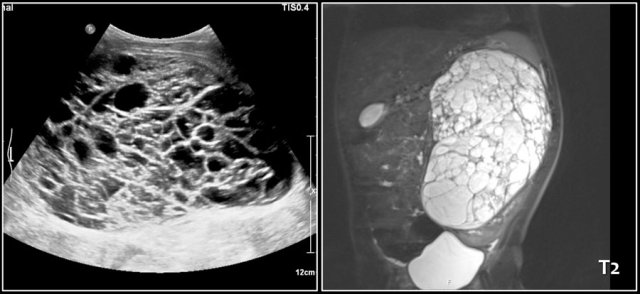

here an one and a half year old girl with a palpable tumor in the left abdomen.

Ultrasound showed a large tumor composed of innumerable cysts, originating from the left kidney.

On a T2 weighted coronal image the cysts are well displayed.

The remainder of the left kidney is at the caudal side of the tumor.

On pathology a cystic partially differentiated nephroblastoma was diagnosed.